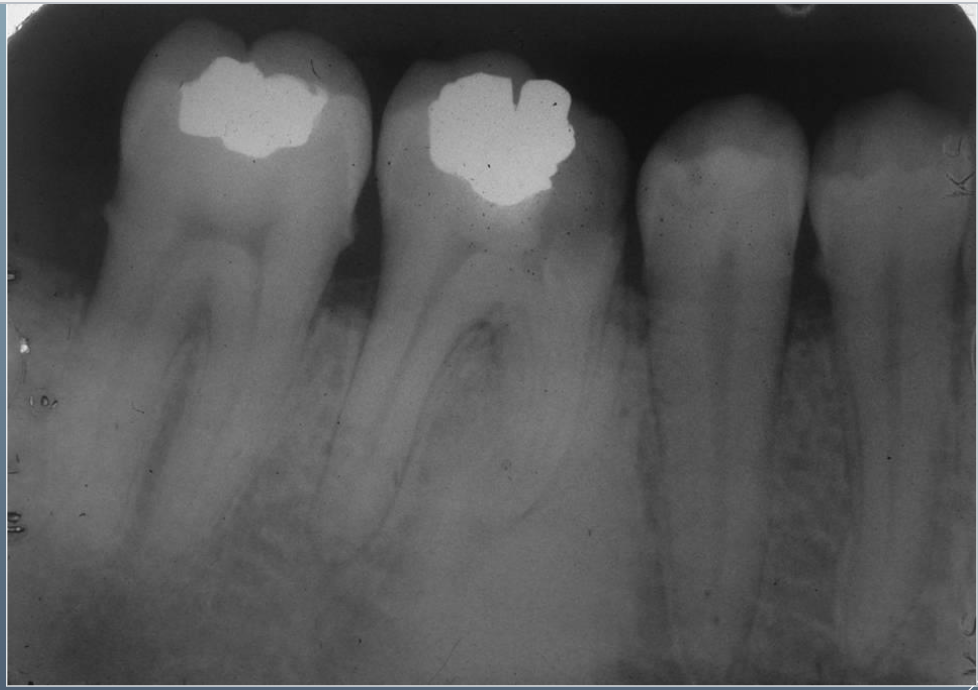

13

Q

What’s ths?

A

IDIOPATHIC OSTEOSCLEROSIS

14

What’s this?

15